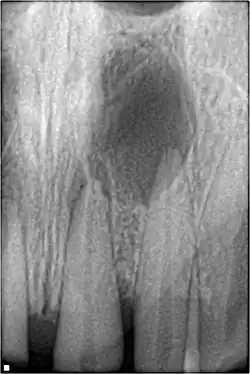

Pulp necrosis usually occurs either as ischaemic necrosis (infarction) caused by disruption to the blood supply at the apical foramen or as an infection-related liquefactive necrosis following dental trauma (2). Signs of pulpal necrosis include[42]

• Persistent grey colour to tooth that does not fade

• Radiographic signs of periapical inflammation

• Clinical signs of infection: tenderness, sinus, suppuration, swelling

Treatment options will be extraction for the primary tooth. For the permanent tooth, endodontic treatment can be considered.

Radiographic signs of periapical inflammation is usually evident in a tooth with necrotic pulp